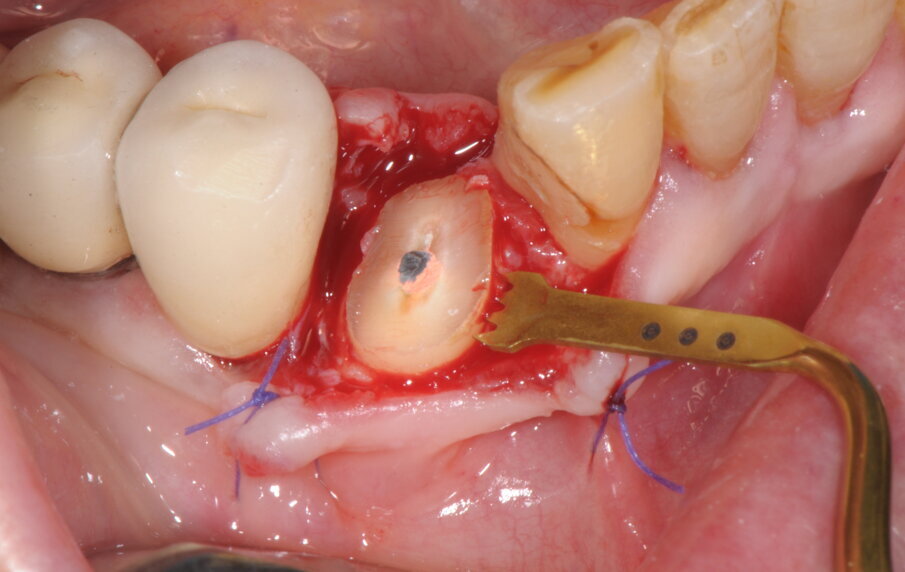

Il caso clinico che andremo a descrivere vede interessata una paziente di anni 69, di sesso femminile, in buona salute, non fumatrice, con frattura del 4.3 ricostruito in precedenza con una ricostruzione diretta in resina composita dopo trattamento endodontico. In accordo con la paziente abbiamo elaborato un piano di trattamento che prevedeva l’estrazione della porzione radicolare residua del canino inferiore di destra, l’inserimento simultaneo di un impianto osteointegrato e un carico protesico immediato. In anestesia locale è stata praticata un’incisione intrasulculare, con minimo scollamento dei tessuti molli, per accedere alla superficie di frattura (Fig. 1). La procedura chirurgica, valutato lo spessore ridotto della corticale vestibolare in accordo con i protocolli PIEZOSURGERY applicati alle estrazioni, ha previsto la regolarizzazione della linea di frattura apicalmente alla giunzione amelo-cementizia, mediante un inserto OT7 e, successivamente, un frazionamento radicolare in direzione mesio-distale con inserto OT7S-3 (Figg. 2, 3).

Fig. 1